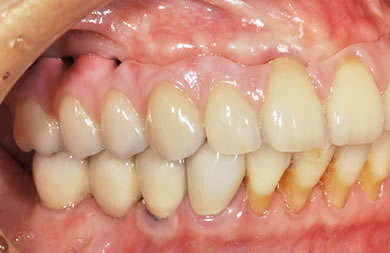

骨再生スピードインプラント治療+AGC連結セラミック治療

| 主訴 | 他院で骨の量が足りずインプラントは難しいと言われ、入れ歯を使用していたが、やはりインプラント治療をうけたい。 | ||||||||||||||||||||||||||||||||

| 治療方針 | 上顎の歯周組織がかなり侵襲されているため、ソケットリフト法にて骨を回復させ、機能的回復だけでなく審美的回復も行うためにAGCハイブリッド連結ブリッジにて補綴処置を行う。 | ||||||||||||||||||||||||||||||||

| 治療内容 | インプラント12本(ソケットリフト+抜歯即日スピードインプラント)、ハイブリッドセラミック8本、AGCハイブリッドセラミック連結ブリッジ1装置、テンポラリーインプラント2本、遊離歯肉移植術 | ||||||||||||||||||||||||||||||||